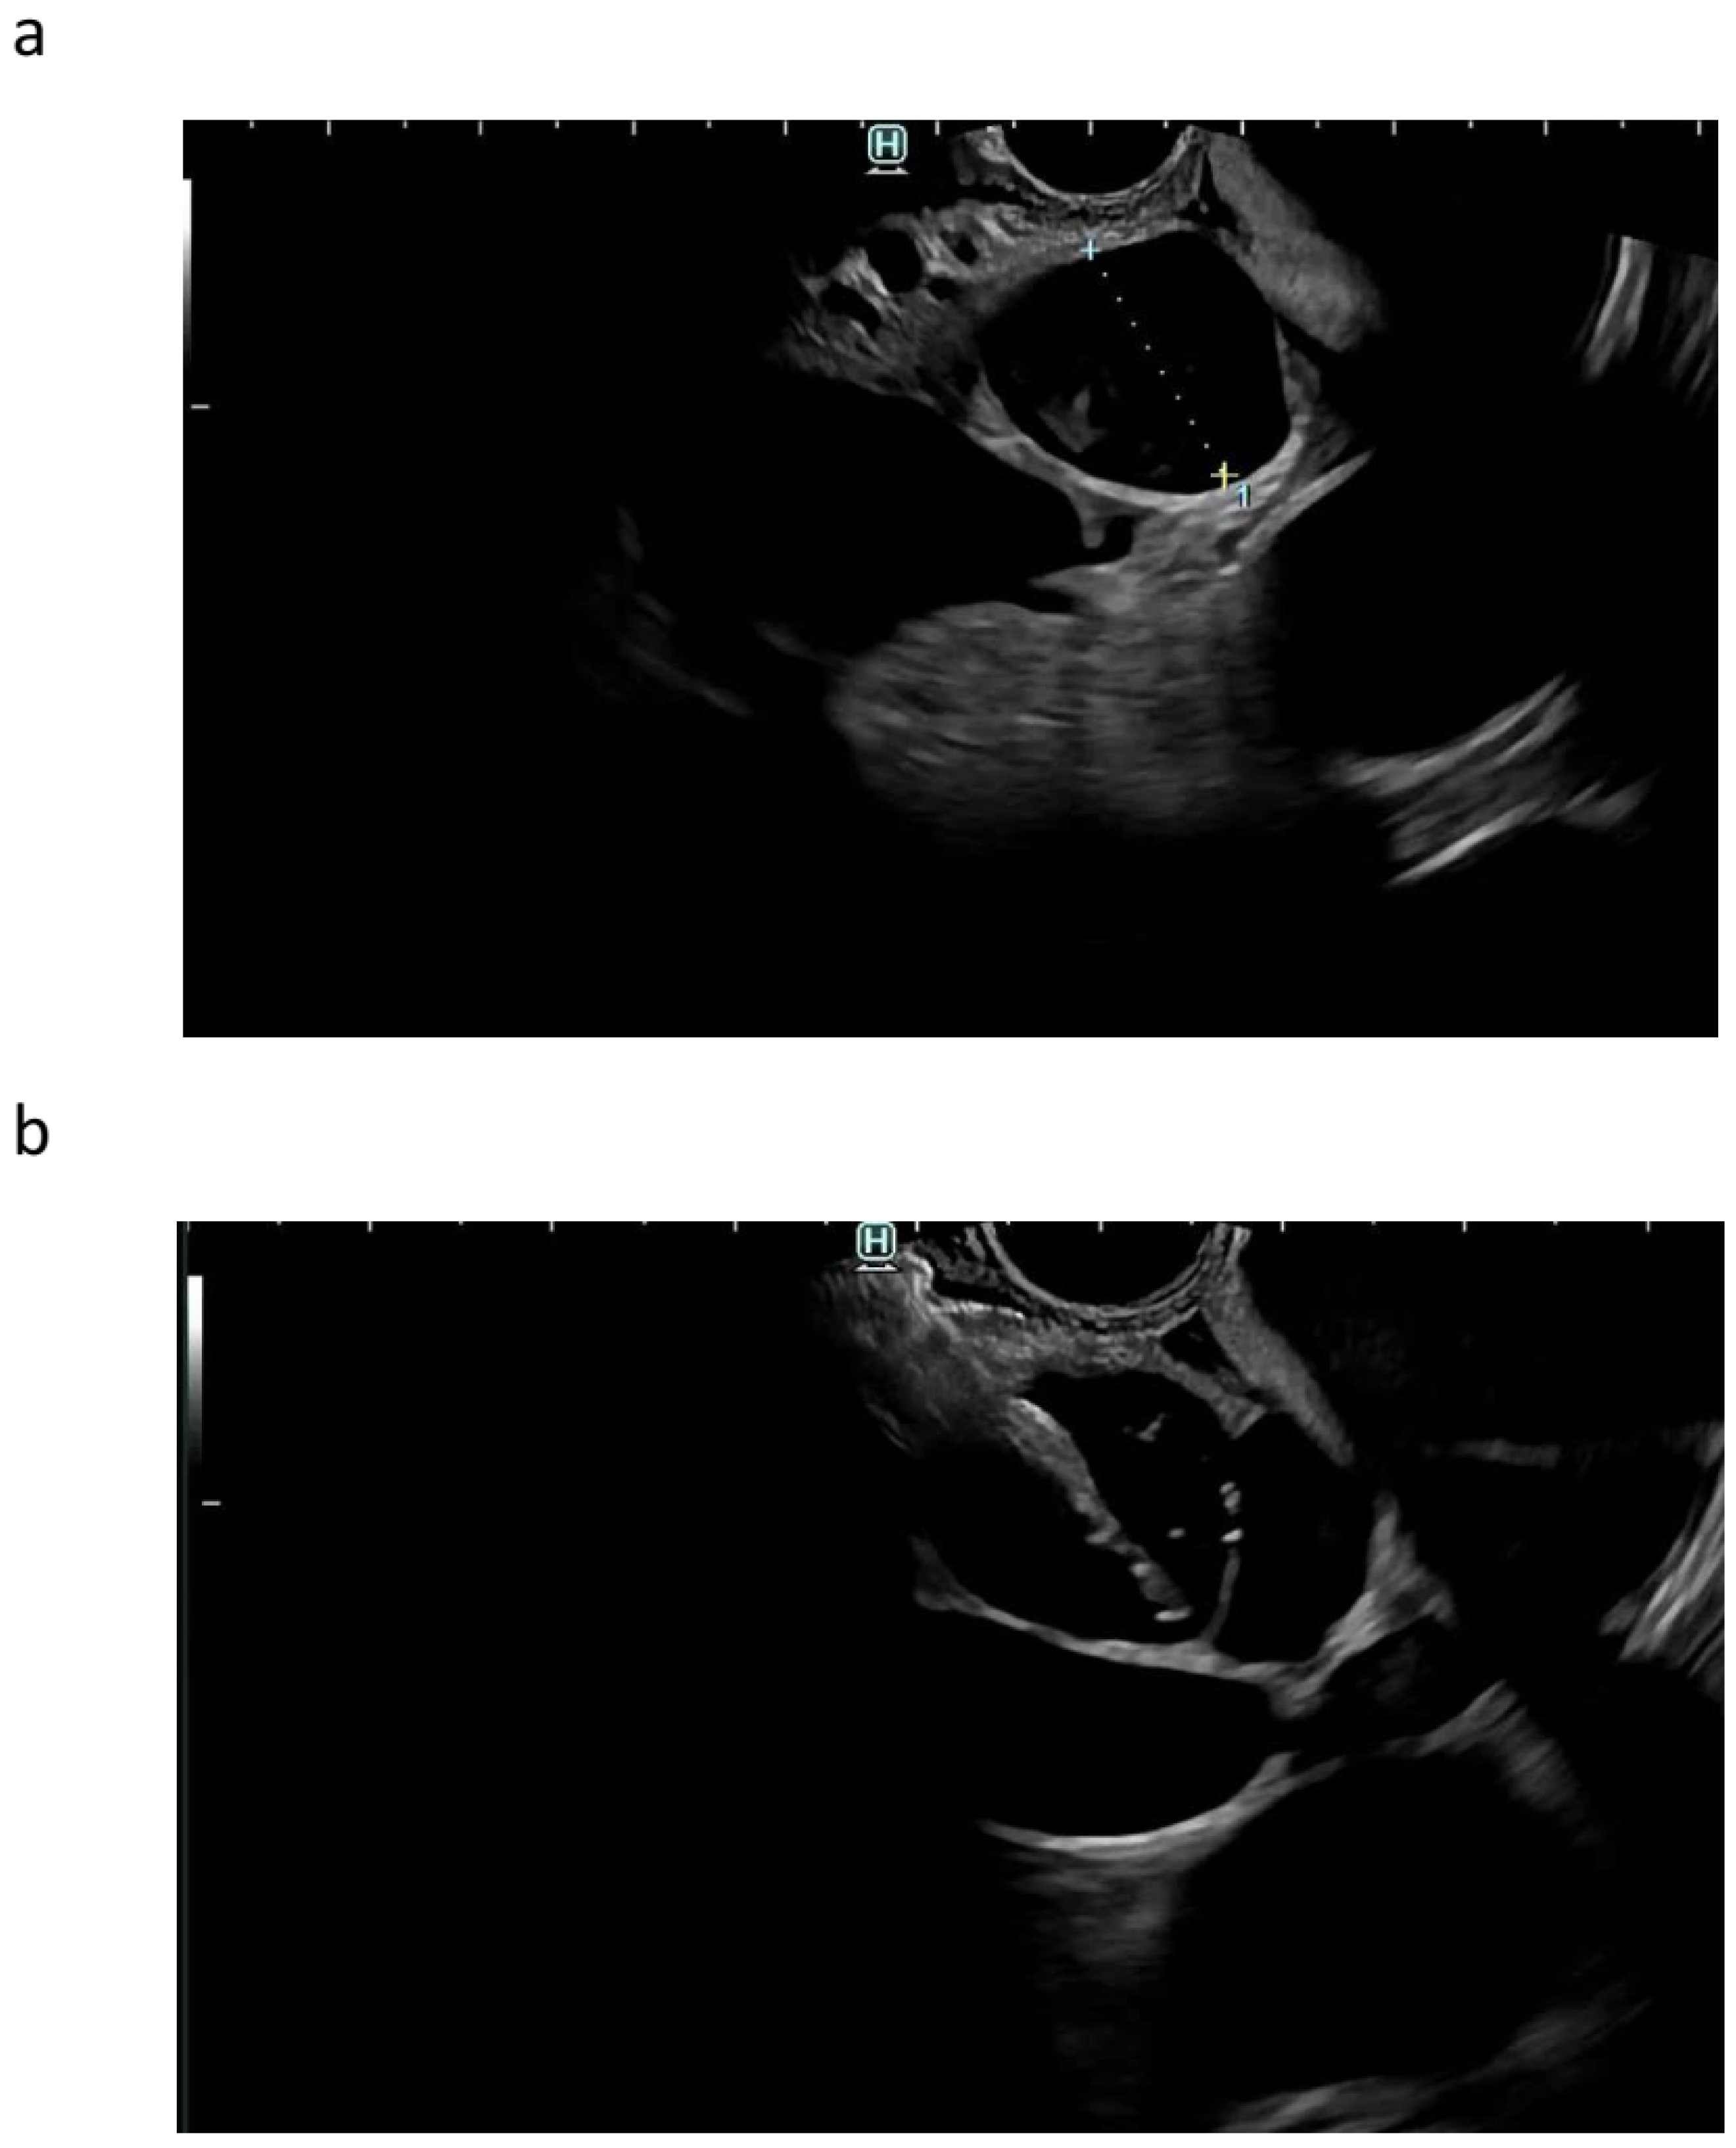

10. Plastic or Metal Stents?

11. Adverse Events